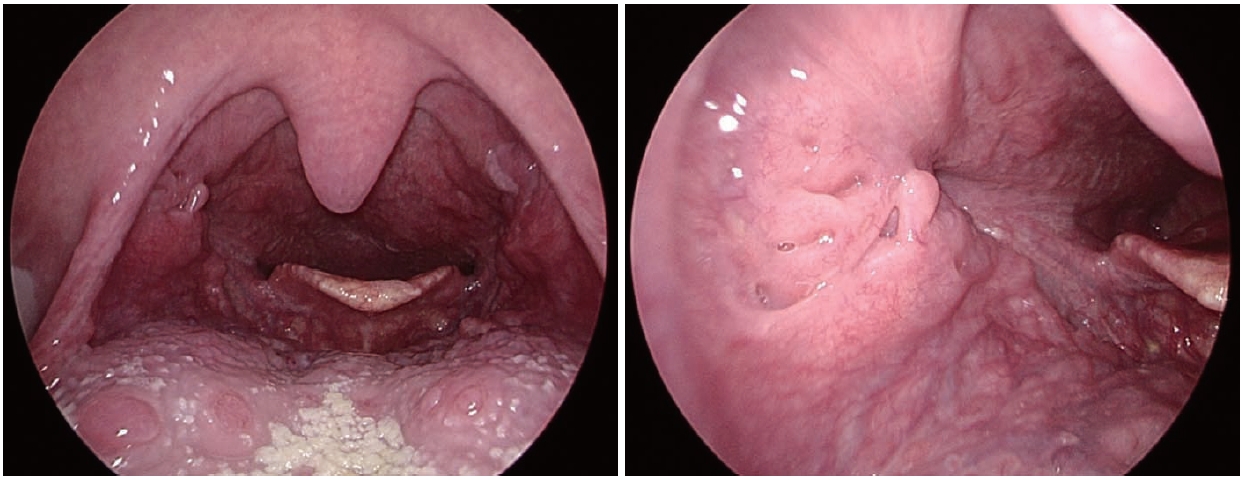

Because a separate primary malignancy of the tonsil was considered, tonsillar biopsy was repeated at our hospital, and poorly differentiated carcinoma consistent with metastatic NSCLC with morphology identical to the lung and mediastinal lymph node lesions was observed. On immunohistochemistry, pancytokeratin was positive and P40 was negative, making primary squamous cell carcinoma of the tonsil unlikely. Vimentin showed focal expression, but according to the pathology interpretation, this did not indicate sarcoma and was interpreted as being related to sarcomatoid features that can be seen in poorly differentiated carcinoma. Based on this immunophenotype and the morphologic similarity to the lung lesion, the lesion was ultimately reported as metastatic disease originating from the lung (Fig. 3). Accordingly, after integrating radiologic and histologic findings, the final diagnosis was tonsillar metastasis originating from the lung.

NotesAcknowledgments This case report was approved by the Institutional Review Board (IRB No.: EUMC 2025-09-061). Author Contribution Conceptualization: Han Su Kim. Data curation: Eun Bin Lee. Investigation: Eun Bin Lee. Methodology: Han Su Kim. Project administration: Eun Bin Lee. Resources: Han Su Kim. Supervision: Han Su Kim. Validation: Han Su Kim. Writing—original draft: Eun Bin Lee. Writing—review & editing: Han Su Kim. Fig. 1.Endoscopic view at the initial outpatient evaluation showing an ulcerative, protruding mass in the right palatine tonsil. Fig. 2.Radiologic findings. A: Contrast-enhanced neck CT showing a 1.8-cm peripherally enhancing, centrally low-density lesion in the right palatine tonsil (yellow arrow). B: Neck MRI showing a 2.3-cm lobulated mass in the right palatine (yellow arrow) tonsil with intermediate T2 signal intensity. C: Chest CT showing a 3.8-cm lobulated mass (yellow arrow) extending across the left major fissure and involving the adjacent pleura. D: PET-CT demonstrating fluorodeoxyglucose uptake in the right palatine tonsil (yellow arrow, SUVmax 21.64), left lower lobe lung lesion (blue arrow, SUVmax 26.41), left hilar lymph node (blue arrow, SUVmax 29.64), and small intestine (green arrow, SUVmax 16.55). Fig. 3.Pathologic findings from the right palatine tonsil biopsy. A: Hematoxylin-eosin–stained specimen showing poorly differentiated carcinoma, favoring metastatic non-small cell lung carcinoma (original magnification ×100). B: Immunohistochemical specimen showing diffuse positivity for cytokeratin pan (CK-PAN), supporting epithelial origin (original magnification ×100). C: Immunohistochemical staining for P40 showing negative results, arguing against a primary squamous cell carcinoma of the tonsil (original magnification ×100). D: Immunohistochemical specimen showing focal vimentin expression, which can be observed in poorly differentiated carcinomas with partial mesenchymal features (original magnification ×100). Fig. 4.Post-treatment radiologic assessment following CCRT. A: Follow-up neck CT showing no residual enhancing mass in the right palatine tonsil (yellow arrow). B: Follow-up chest CT showing a decreased size of the previously noted lobulated mass (yellow arrow) extending across the left major f issure. REFERENCES1. Unsal M, Kutlar G, Sullu Y, Yurtlu S. Tonsillar metastasis of small cell lung carcinoma. Clin Respir J 2016;10(6):681-3.